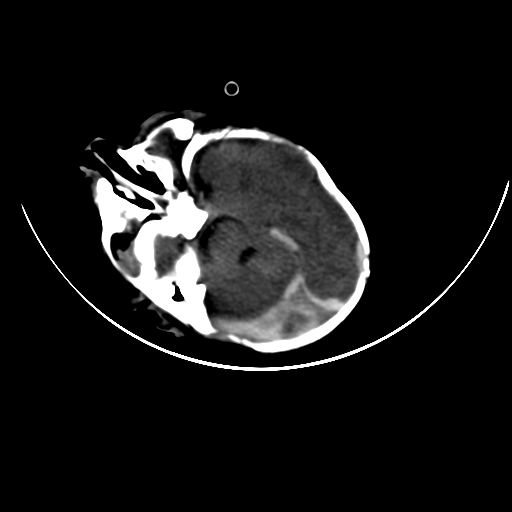

双侧硬膜下血肿并蛛网膜下腔出血。

双侧硬膜下血肿并蛛网膜下腔出血

硬膜下及蛛网膜下腔出血。

hie 蛛网膜下腔出血,硬膜下血肿。

hie;双侧硬膜下血肿并蛛网膜下腔出血

hie,双侧硬膜下血肿并蛛网膜下腔出血

双侧硬膜下血肿并蛛网膜下腔出血,考虑维生素k缺乏引起.

较大范围出血,应考虑维生素k缺乏引起,结合临床吧。

好像脑实质没有明显低密度影,各位大侠怎么支持hie呢?